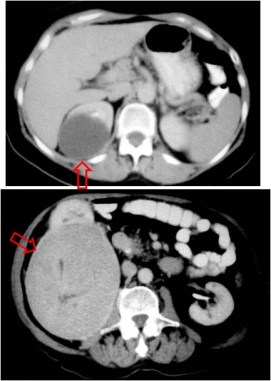

SIGNO DEL BORDE FINO

Signo de masa renal en la urografía intravenosa y en la arteriografía. El quiste simple de gran tamaño, que se extiende más allá de los límites del riñón, está rodeado de un borde de 1 ó 2 mm de tejido que se opacifica con el contraste. Este realce está producido por la acumulación del material de contraste en nefronas comprimidas y en pequeños vasos de la parte fibrosa de la cápsula renal.

Aunque fue descrito en el quiste simple, también puede verse en masas sólidas.

Otro ejemplo de este signo en un paciente con poliquistosis renal.

En la TC el signo es visible tanto en lesiones benignas (como el quiste simple de la imagen de arriba) como en malignas (carcinoma renal, abajo). Su interés consiste en confirmar el origen renal de las lesiones, no siempre fácil de determinar en las de gran tamaño y crecimiento extrarrenal.